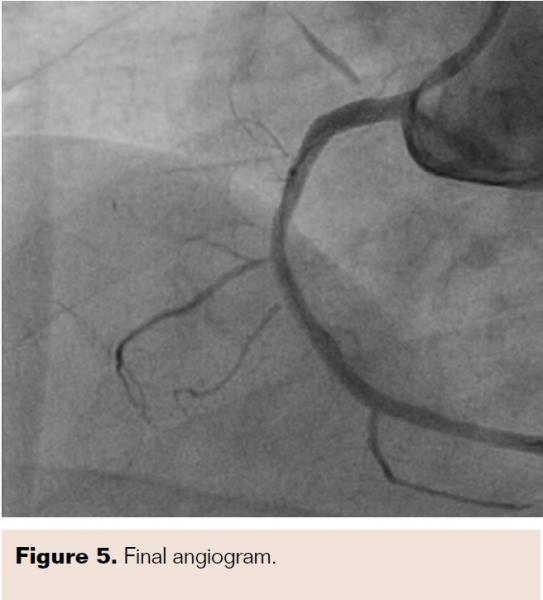

He was admitted and was managed for acute coronary syndrome – unstable angina. He was managed as per guideline-directed medical treatment and was later taken for coronary angiogram after written informed consent. A precatheterization profile was performed and a radial approach with a 5 Fr Tiger catheter (Terumo) was chosen. The left coronary system showed no significant lesions, but Mehran type III in-stent restenosis (ISR) was noted in the ostioproximal RCA stent (Figure 1). Accordingly, the decision was made to proceed with repeat PCI, and when the 6 Fr Judkins right 3.5 guide catheter (Medtronic) was exchanged and manipulated, the patient reported severe chest pain. Echocardiogram showed ST elevation in inferior leads. The check angiogram showed ostial right coronary total occlusion (Figure 2A), so the RCA was quickly wired with a 0.014" balance middle weight floppy wire (Abbott Vascular) and the ostioproximal lesion was predilated with a 2 mm x 10 mm Sprinter Legend semicompliant balloon (Medtronic) (Figure 2B). Postdilatation cine showed a longitudinal homogenous opacity moving from the proximal RCA and embedded into the distal RCA, causing TIMI 0 flow (Figures 2C and 2D). Because the first differential for TIMI 0 flow was thrombotic occlusion, our strategy was to disintegrate the thrombus via balloon manipulation. After failure on multiple attempts, thrombosuction with a 6 Fr, 140 cm Thrombuster II (Kaneka Medix Corp.) was performed and a pale soft tissue was retrieved (Figure 3A). Imaging post thrombosuction showed clearing of the ISR and TIMI III flow across the RCA (Figure 4). Histopathology of the retrieved tissue reported endothelial cells with intermittent muscle cells (Figure 3B). The ostioproximal RCA was stented with a 3 mm x 18 mm Xience Pro everolimus-eluting coronary stent (Abbott Vascular) and TIMI III flow was noted with resolution of chest pain and ECG changes (Figure 5). The patient was closely monitored for 48 hours and was discharged.